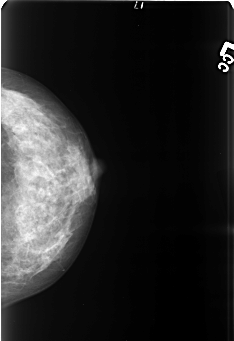

Digital Database for Screening Mammography

Volume: benign_06 Case: B-3419-1

B_3419_1.LEFT_CC

LEFT_MLO LINES 4360 PIXELS_PER_LINE 2960 BITS_PER_PIXEL 12 RESOLUTION 50 NON_OVERLAY